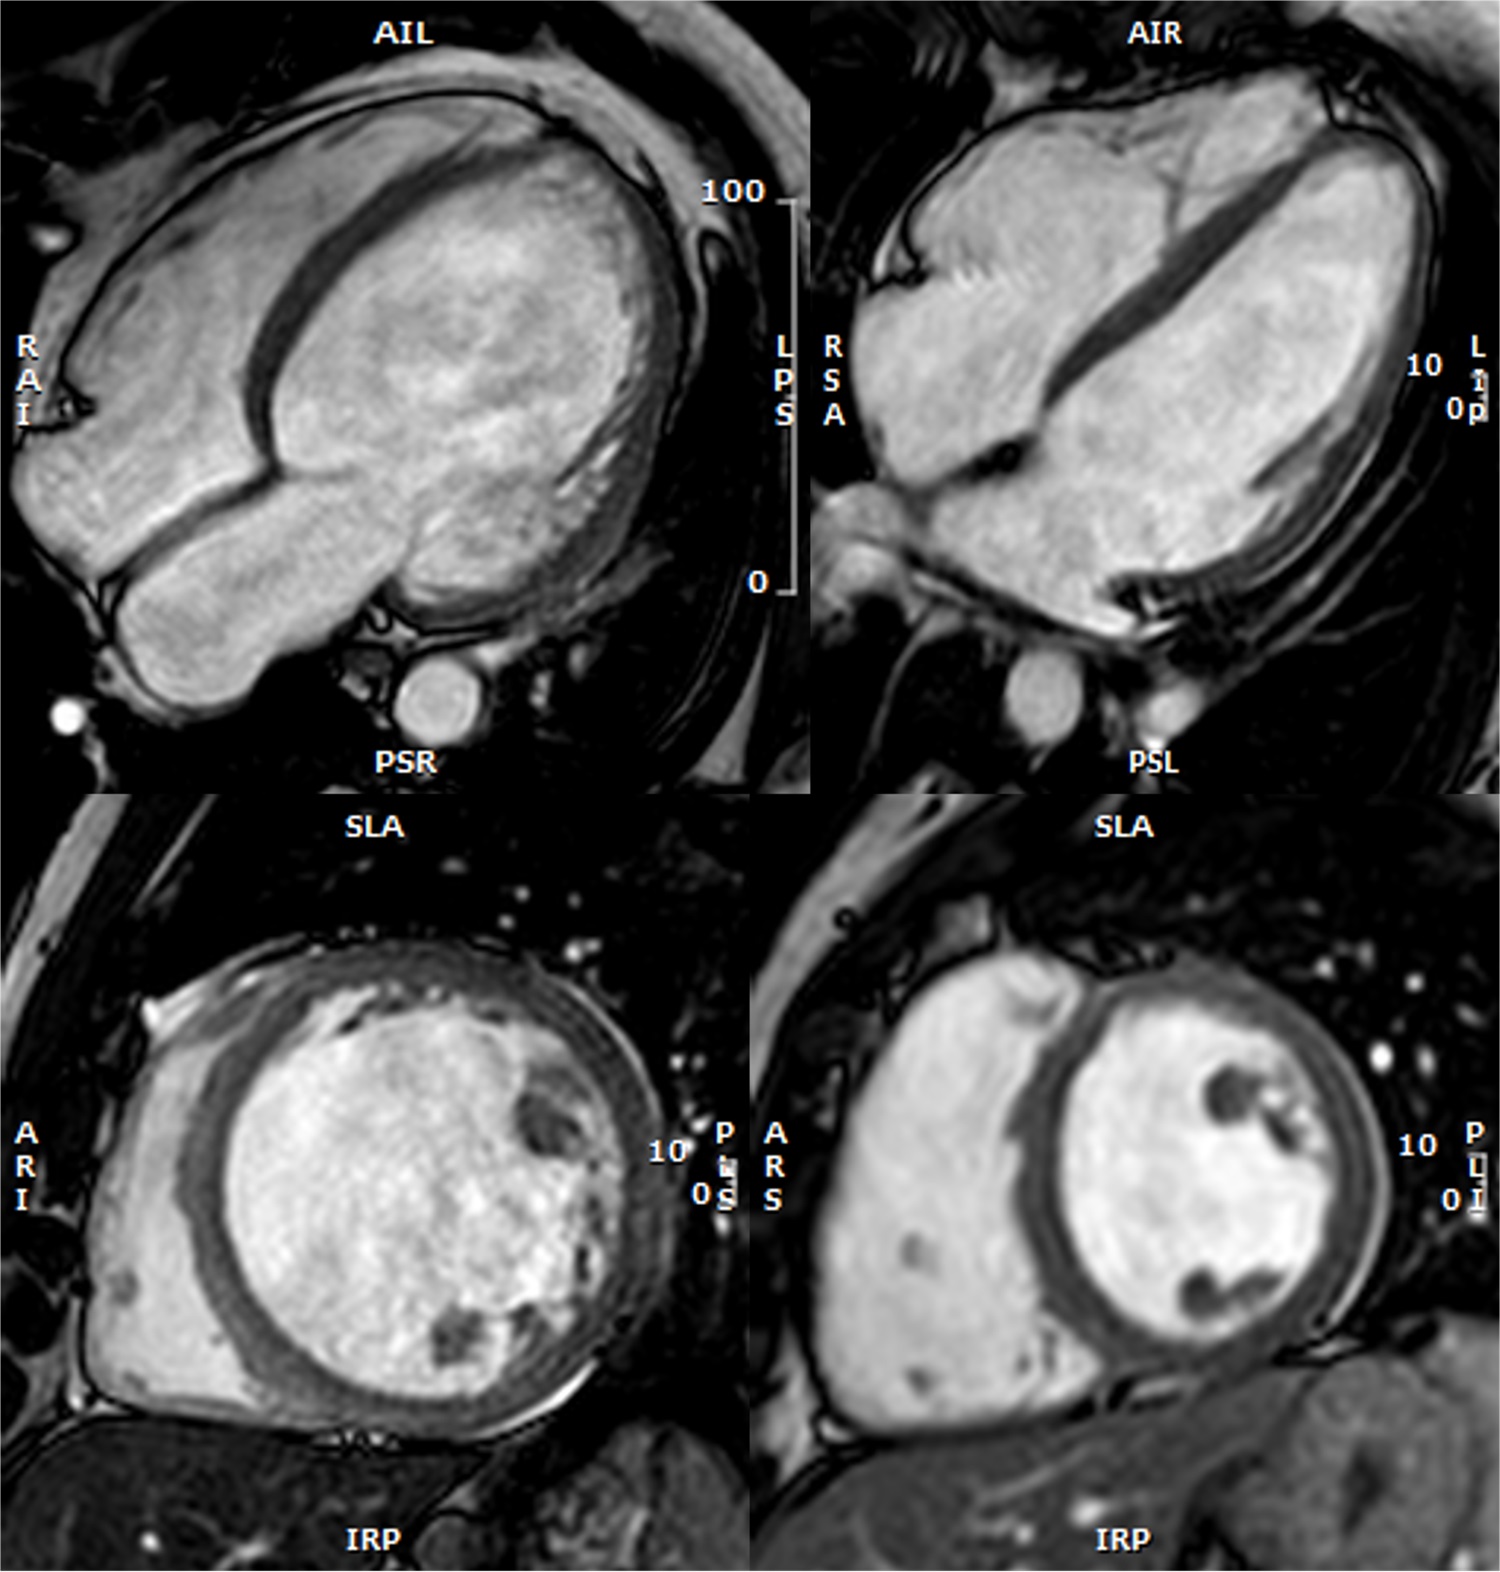

Research 4 Feb 2025 The study, published in JACC: CardioOncology, shows that administration of the SGLT2 inhibitor empagliflozin to pigs receiving anthracyclines preserves mitochondrial function, improves myocardial energetics, and prevents degenerative changes in heart structure |